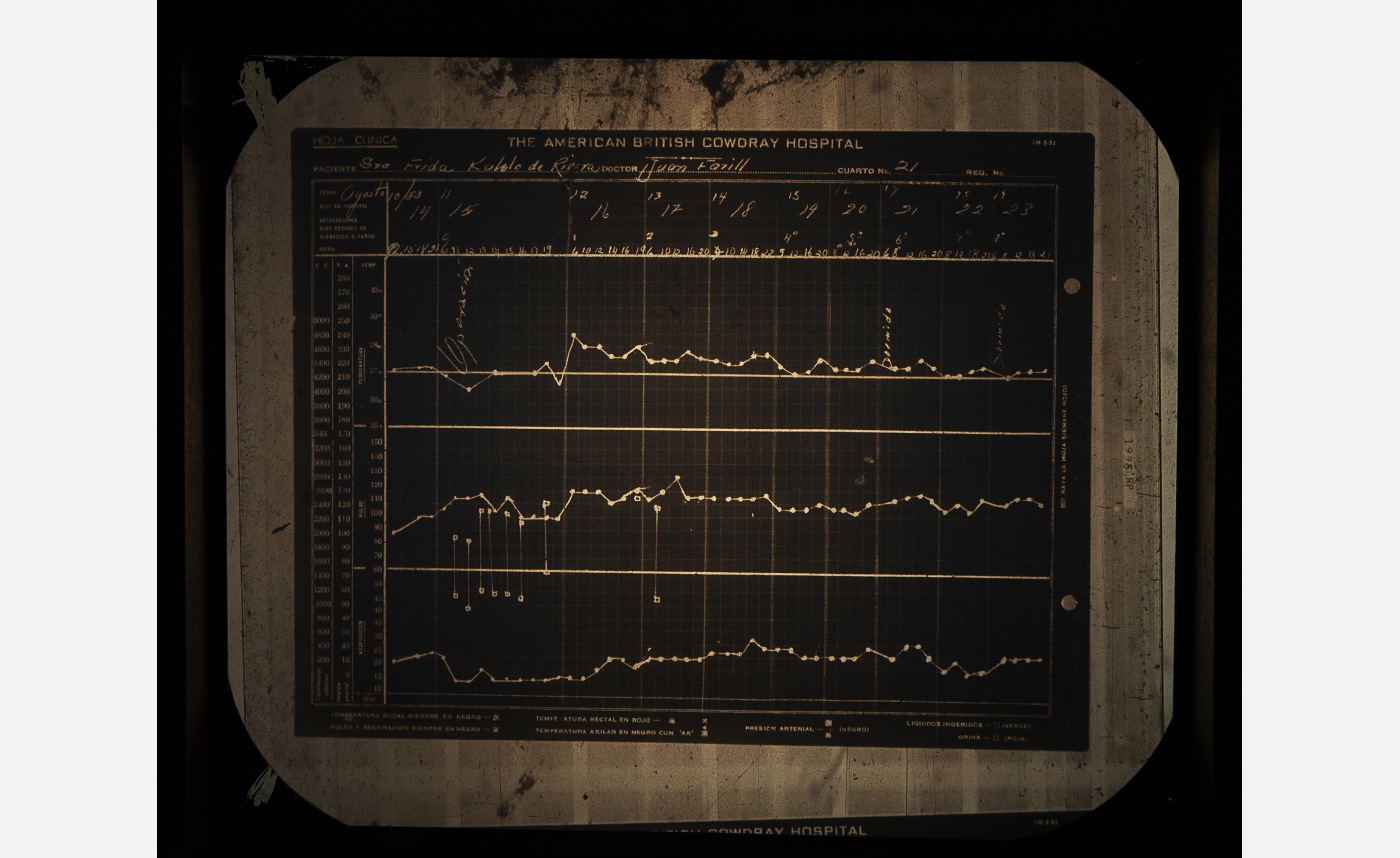

Her Lower Limbs

At the age of 6, Frida Kahlo contracted polio virus, resulting in her right leg being shorter and thinner. This physical disability was further complicated by the streetcar accident, in 1925, that caused 11 fractures in her right foot. As a result, Frida lived with chronic pain in her lower limbs, often having to be treated for foot ulcers that were largely due to vascular insufficiency. Eventually doctors amputated five phalanges, or bones in Frida’s right foot as well as a smaller bone, the sesamoid.

The last major recorded surgery Frida Kahlo underwent was an amputation of her right leg, on 11 August 1953—less than a year before her passing. The amputation was performed due to Frida having been diagnosed with gangrene—a medical condition that involves the death of body tissue due to a lack of blood flow or a serious bacterial infection.

Cristina Kahlo Alcalá, American British Cowdray Hospital File (Clinical Sheet), 1953, 2023, lightbox installation, Courtesy of the artist and Centro Médico ABC Historical Archive. © Cristina Kahlo

Cristina Kahlo Alcalá, American British Cowdray Hospital File (Clinical Sheet), 1953, 2023, lightbox installation, Courtesy of the artist and Centro Médico ABC Historical Archive. © Cristina Kahlo -

Cristina Kahlo Alcalá, American British Cowdray Hospital File (Clinical Sheet), 1953, 2023, lightbox installation, Courtesy of the artist and Centro Médico ABC Historical Archive. © Cristina Kahlo

Cristina Kahlo Alcalá, American British Cowdray Hospital File (Clinical Sheet), 1953, 2023, lightbox installation, Courtesy of the artist and Centro Médico ABC Historical Archive. © Cristina Kahlo

The Hospital

Frida Kahlo spent a large part of her adult life in hospitals following her near fatal streetcar accident in 1925, resulting in lifelong medical complications and chronic pain. Frida was regularly admitted into and discharged from medical facilities throughout her life. Notable hospitals include the Henry Ford Hospital in Detroit and the American British Cowdray (ABC) Hospital in Mexico City.

The ABC hospital was where Frida stayed for almost a year in 1950—undergoing seven spinal surgeries—and where in 1953 her lower right limb was amputated under the care of Dr. Juan Farill. Frida was treated at the ABC hospital until her passing in 1954.